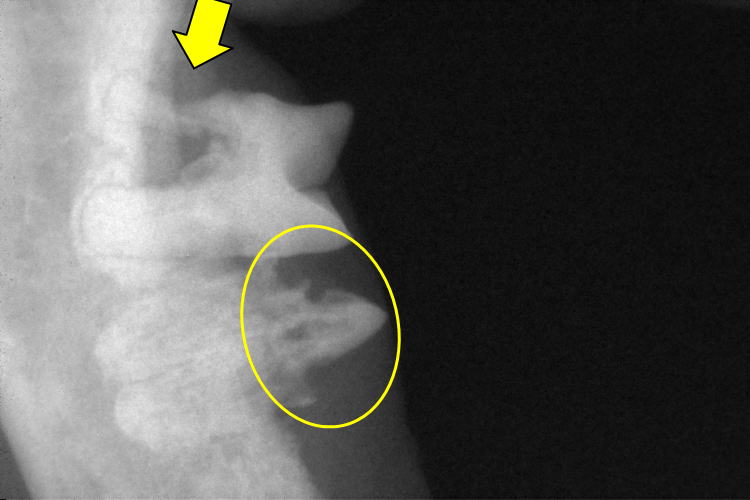

右下顎第2前臼歯(写真上側の歯)と第1後臼歯(写真下側の歯)です。

第2前臼歯は近心根が細くなり(黄色矢印)、吸収している事が確認出来ます。

第1後臼歯は歯冠が吸収し(黄色〇)、歯根はアンキローシスを起こしていました。